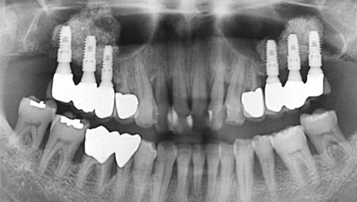

전악 임플란트

전체 치아 상실 시

W Dental Clinic Before & After

치료 전후사진

Before

After

뼈이식